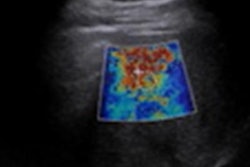

Researchers in Tokyo presented results of a study examining the potential of ultrasonic parameters on 2D shear-wave elastography in diagnosing biopsy-proven nonalcoholic fatty liver disease. The results were shown at the RSNA annual meeting. Here, shear-wave speed and dispersion slope are compared in assessing lobular inflammation. Image courtesy of Dr. Katsutoshi Sugimoto.The researchers found that the combination of all three parameters showed an area under the curve (AUC) of 0.791 for the diagnosis of nonalcoholic steatohepatitis.

Individually, the parameters showed variable performance. For example, dispersion slope had an AUC of 0.696 for identifying moderate lobular inflammation and 0.920 for identifying marked inflammation. Shear-wave speed meanwhile yielded superior performance for moderate (AUC, 0.708) and lower-grade inflammation (AUC, 0.779). For marked inflammation, shear-wave speed had an AUC of 0.917.